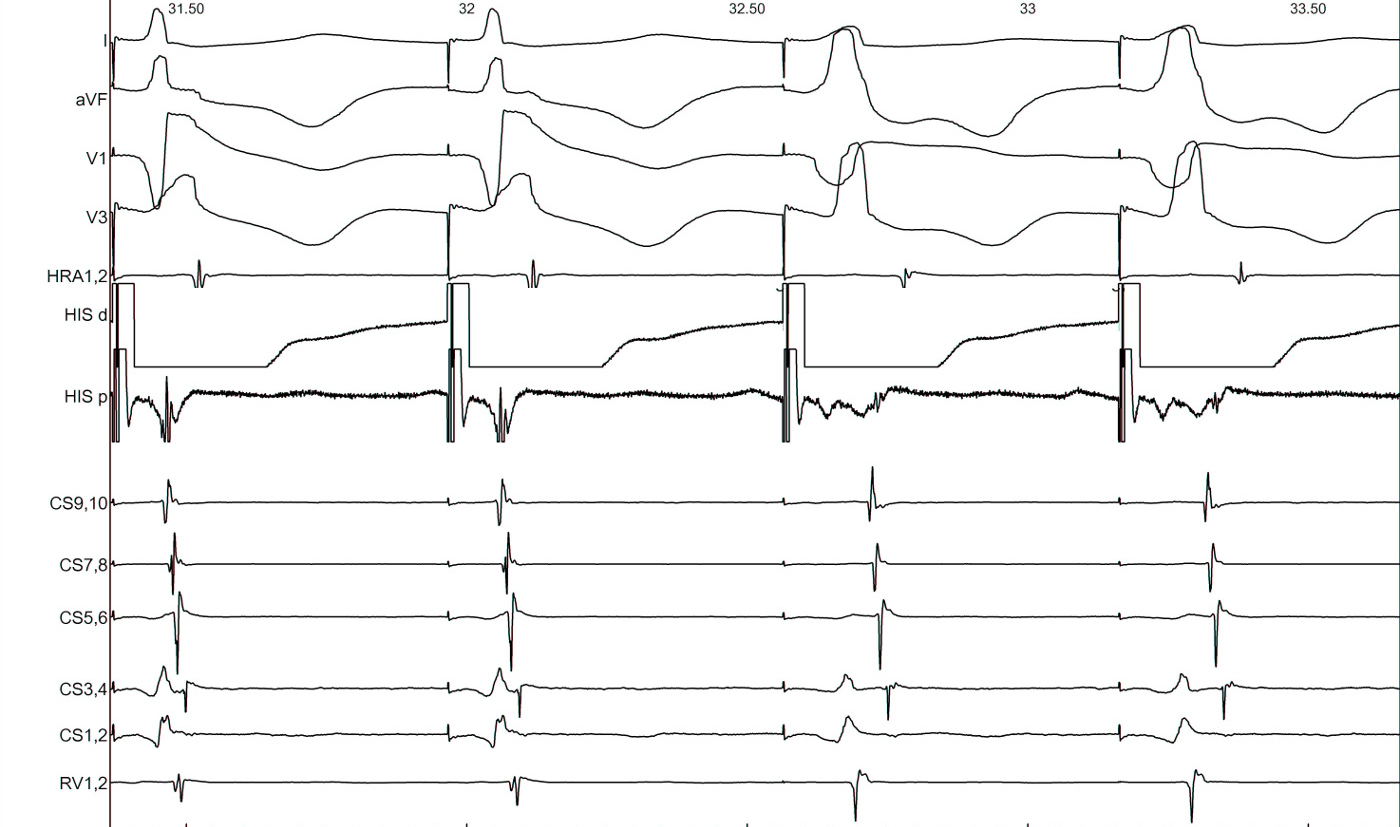

RV 500/300 ms

rv500_300.jpg

RV 500/280 ms

rv500_280.jpg

RV 500/260 ms

rv500_260.jpg